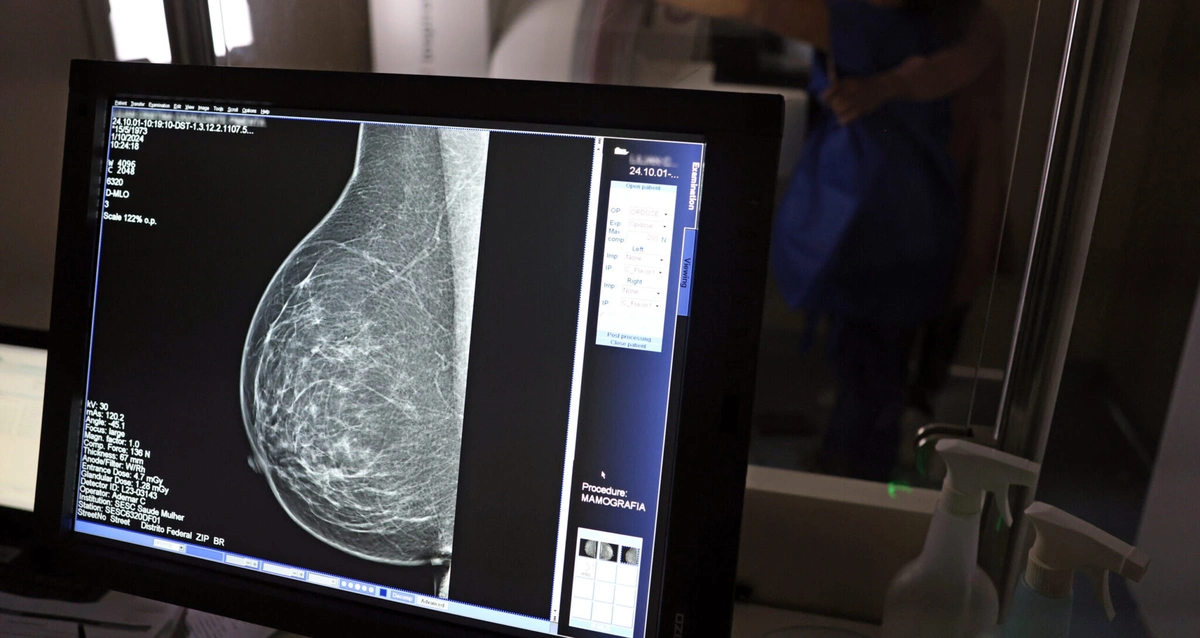

Estado amplia diagnóstico precoce e reforça tratamento contra doença.Com mais de 57 mil mamografias realizadas em 2025, o Piauí ampliou significativamente o acesso ao diagnóstico precoce do câncer de mama, especialmente entre mulheres a partir dos 40 anos. Como parte das ações de reforço ao tratamento, o estado recebeu, na quinta-feira (23), uma remessa com 224 unidades do medicamento Trastuzumabe Entansina, recém-incorporado ao Sistema Único de Saúde (SUS) para casos avançados da doença.

A rede estadual conta com 43 mamógrafos fixos e o serviço itinerante dos Caminhões da Mamografia, que percorrem os municípios levando o exame a quem mais precisa. O foco principal tem sido nas mulheres entre 40 e 49 anos, faixa etária que passou a ser atendida sob demanda, conforme nova orientação do Ministério da Saúde.